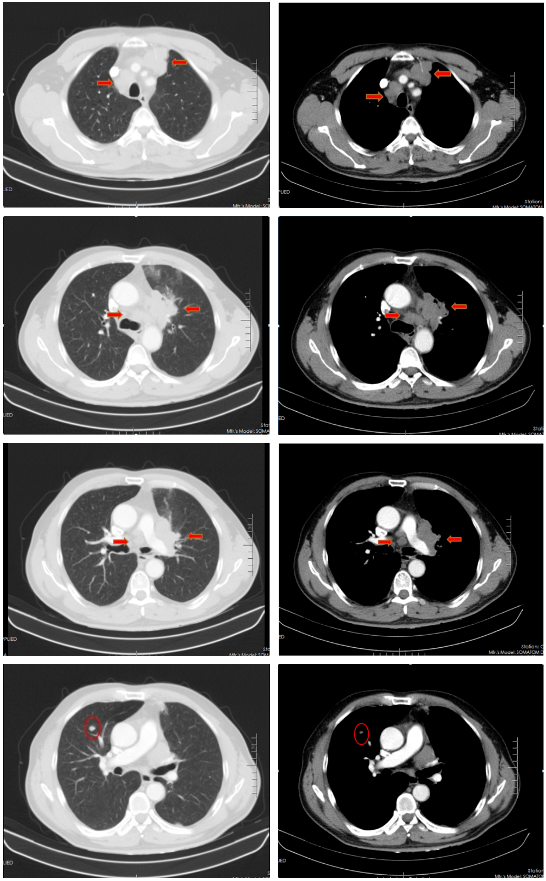

2022-04-14、2022-05-12、2022-06-09、2022-07-07应用斯鲁利单抗 300mg+顺铂(40mg d1-3)+依托泊苷(100mg d1-5)治疗4周期。

胸部CT(2022-07-15):双侧肺野透亮度增加,以两上肺和胸膜下明显。双肺纹理增多、增粗,紊乱,左肺上叶条片状高密度灶,大小约45mm×19mm,小叶间隔增厚。气管、左右主支气管无明显狭窄。纵隔内未见肿大淋巴结影。两侧胸腔无明显积液。胸部CT诊断:左上肺门占位复查;慢性支气管炎-肺气肿样改变。

治疗后评价:患者经过EP方案联合斯鲁利单抗治疗四周期后,患者咳嗽、咳痰及左侧胸痛症状消失,体重逐渐恢复;影像学提示左肺病灶及纵膈淋巴结及肺门淋巴结较前明显缩小(缩小>30%),右肺结节基本消失;疗效评价:PR(接近CR)。